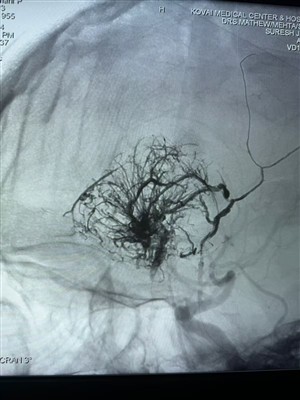

Premier cas de tumeur hypervasculaire signalé en IndeHeureux de partager ce premier cas de tumeur hypervasculaire réalisé en Inde. Il a été traité avec le système Lava Liquid Embolic de NeuroSafe Medical Co., Ltd.. Merci au Dr Mathew Cherian. Il a ét...